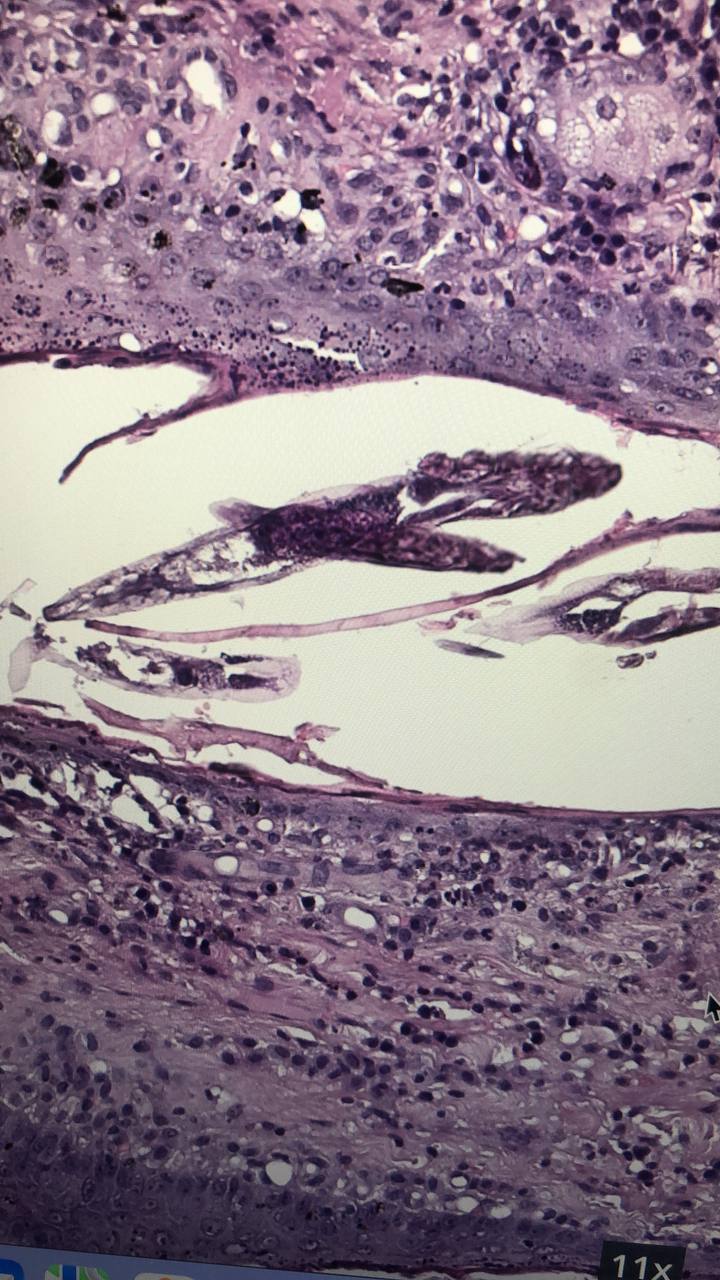

Редкая нынче находка, особенно в гистологических препаратах. Клещи рода Demodex